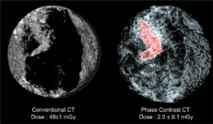

Comparación entre un escáner convencional de mama (izquierda) con uno obtenido con el nuevo método. Fuente: ESRF-LMU/Brun.

Los científicos aplicaron este procedimiento para conseguir imágenes del pecho de una mujer de 75 años con un cáncer ductal invasivo, que “es el tipo de cáncer más frecuente”, explican, y representa más del 70% de los cánceres malignos de mama. Su objetivo era reducir la dosis de radiación sin que la calidad de la imagen se viera mermada, algo que han conseguido.

Después, las imágenes obtenidas fueron evaluadas a ciegas por cinco radiólogos independientes de la universidad alemana, quienes afirmaron que tenían mayor brillo, contraste y calidad en comparación con imágenes en tres dimensiones generadas por otros métodos.